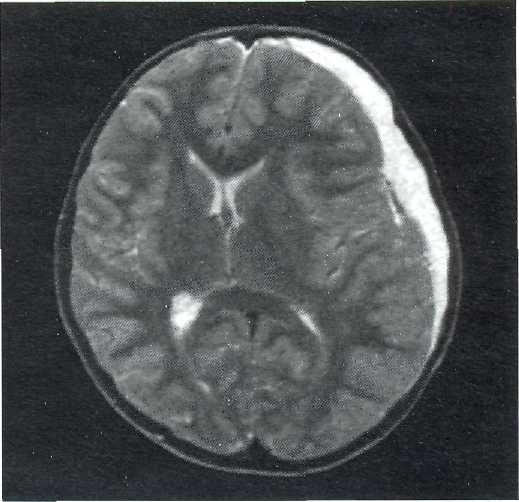

Медицинские аспекты и диагностика субдуральной гигромы мозга